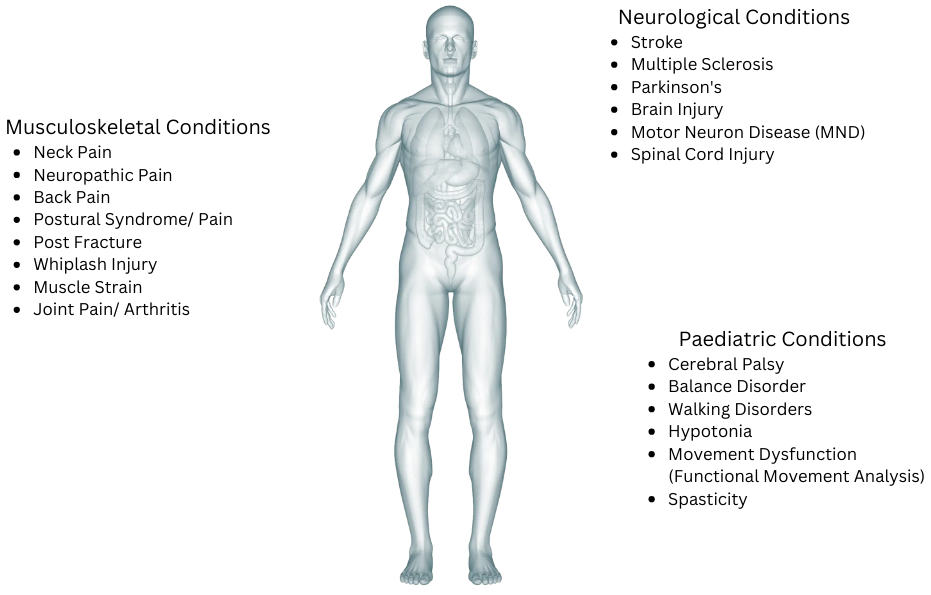

Explore Our Treatment Specialties

The diagram below highlights the range of musculoskeletal, neurological, and paediatric conditions we expertly treat at HM Rehab Basics